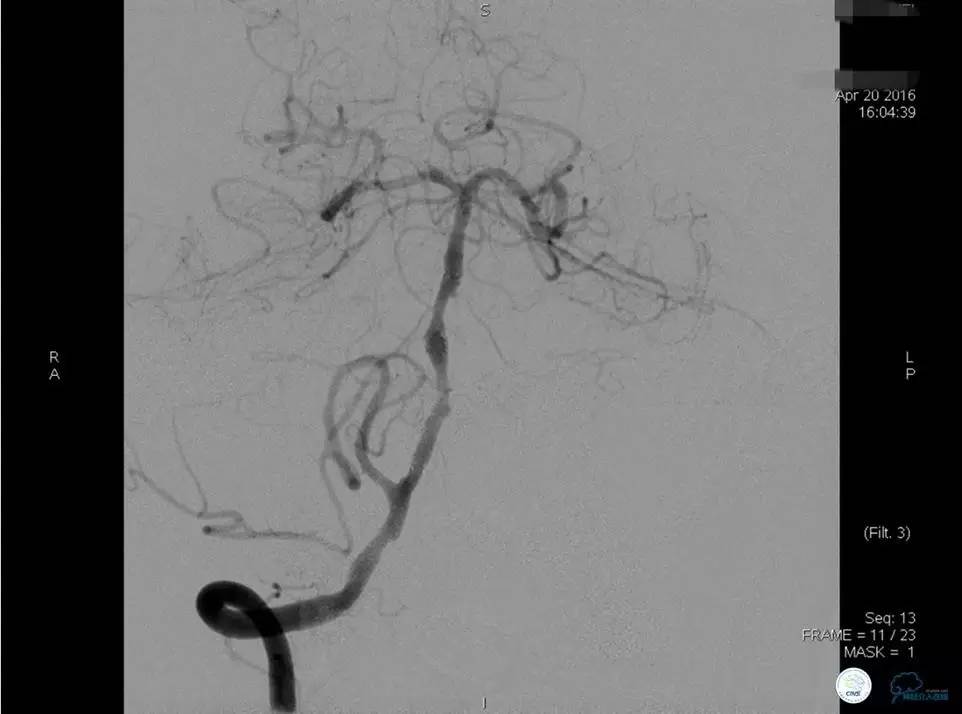

患者:58岁男性,反复头晕、肢体无力3月,当地造影见多发颅内动脉狭窄、闭塞,转来我院。

▼首先行颈动脉CTO开通术,手术顺利,Wallstent支架。

▼1周后行右侧椎动脉V4段CTO开通术。

▼微导丝穿过狭窄段,微导管造影,小球囊预扩张,2mm。

▼根据血管情况选择较大球囊再次预扩张。

▼置入2枚Wingspan支架,手术成功。

▼术后即刻CT,梗死灶内再灌注出血。

患者无症状,中性治疗。4月21日电话随访,一般情况好,当地CT示出血吸收期。